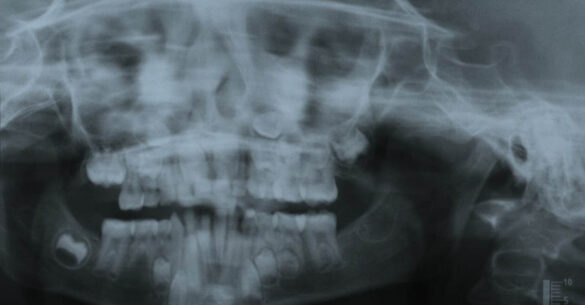

La momentul prezentării în clinică, în decembrie 2002, pacienta avea 8 ani şi o lună şi suferea de fibroză chistică şi de o deficienţă de dezvoltare a etajului mijlociu al feţei. Aceasta prezenta o anomalie de clasa I care mima o anomalie de clasa a III-a. Incisivii centrali, laterali şi caninii temporari maxilari, precum şi molarii prim şi secund de pe partea stângă erau în ocluzie inversă. În plus, pacienta prezenta coloraţii ale dinţilor de etiologie idiopatică (fig. 1). Autorii au considerat coloraţiile ca fiind de suprafaţă, extrinsece şi nu determinate de fibroza chistică, dovadă îndepărtarea acestora prin periaj profesional. Radiografia panoramică efectuată cu 6 luni înainte de prezentarea în clinica stomatologică relevă anodonţia incisivilor laterali superiori şi a premolarului secund drept inferior, ca şi posibila incluzie a caninilor maxilari, în special a celui stâng (fig. 2).